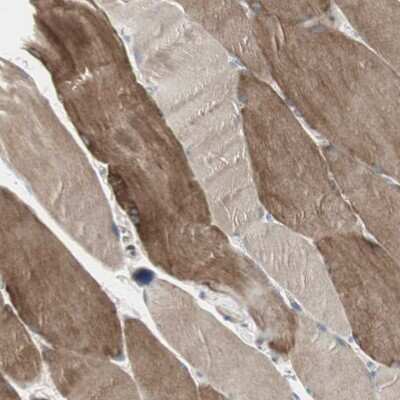

Immunohistochemistry-Paraffin: DMPK Antibody [NBP1-85011] - Staining of human skeletal muscle shows moderate cytoplasmic positivity in myocytes.